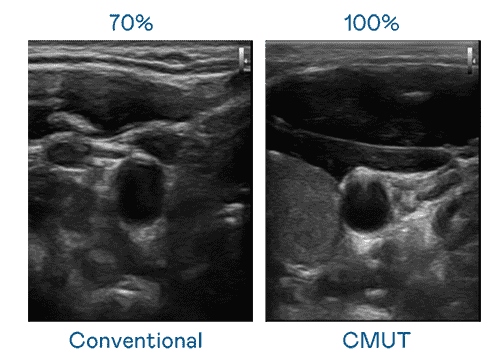

CMUT 技术是一种用电容式微机电元件来产生超音波讯号的技术。。。。与传统 PZT 压电式技术相比,,,CMUT 频宽增加 30%,,,,更宽频的超音波讯号让影像解析度大幅提升,,,是实现高影像品质医疗超音波扫描、、、促进精准医疗发展的关键技术。。。

大频宽带来超清晰影像

超音波影像的解析度高低,,,首先取决于探头能发出的讯号频宽。。。龙门国际 CMUT 可提供高清晰的超音波讯号,,提供高频宽、、、、高灵敏度、、影像纹理细节更高的超音波影像,,协助医护人员缩短影像判读时间及利用精准的医疗影像进行诊断。。。